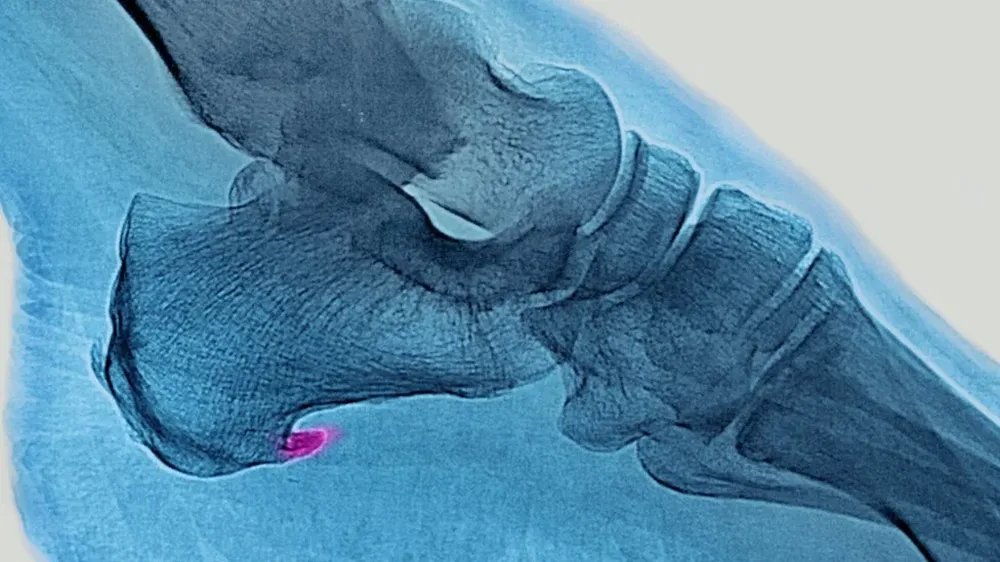

Se trata de un dolor agudo en la planta del pie, justo por delante del talón, que se intensifica cuando nos levantamos o pasamos un período de tiempo sin movernos.

Lo que ocurre es que se produce una inflamación de la membrana que recubre la musculatura de la planta del pie y el talón.

La inflamación se produce cuando se trata compensar con los músculos del pie y sus tendones un desbalance que ocurre en el cuerpo.

Eso se debe a que la fascia plantar cumple una función biomecánica al caminar de absorber y devolver la energía que se produce cuando el pie impacta contra el suelo.